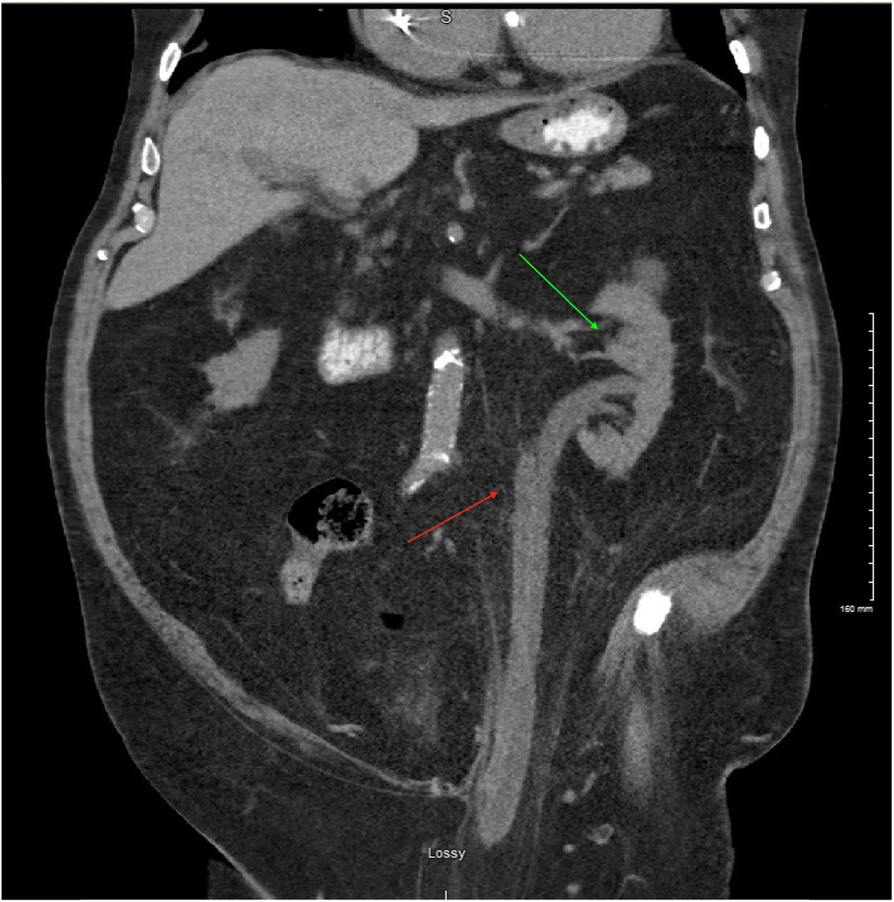

CT scan of the abdomen and pelvis showing the hydroureternephrosis. (Green arrow: Hydronephrosis, Red arrow: ureteronephrosis)